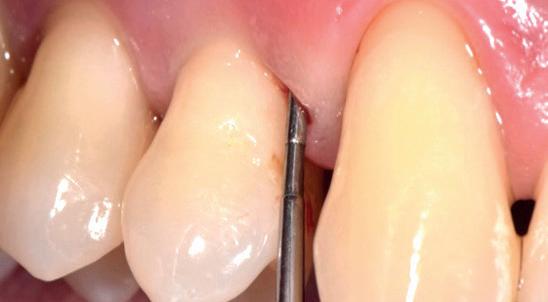

Een 48-jarige gezonde vrouw presenteerde zich in de nazorgfase 2 jaar na initiële behandeling met pockets van 6–7 mm en furcatieproblematiek bij de 47 en 46 (afbeelding 1.1 en 1.3). Bloeding bij sonderen was aanwezig, maar de patiente wilde geen chirurgische behandeling. Ze hield er een keurige mondhygiëne op na en kwam trouw iedere drie maanden voor nazorg.

De pockets werden onder lokale anaesthesie behandeld met een combinatie van ultrasoon en handinstrumentarium volgens de hierboven beschreven methode. De natriumhypochloriet/aminozuur-gel werd vijfmaal aangebracht en na iedere applicatie mechanisch verwijderd. Daarna werd de pocket gevuld met cross-linked hyaluronzuur.

Na 6 maanden was de pocketdiepte teruggebracht tot 3 mm en was er geen bloeding na sonderen waarneembaar. Een recessie van 2 mm was aanwezig. Röntgenologisch was er nieuw bot zichtbaar (afbeelding 1.2 en 1.4).